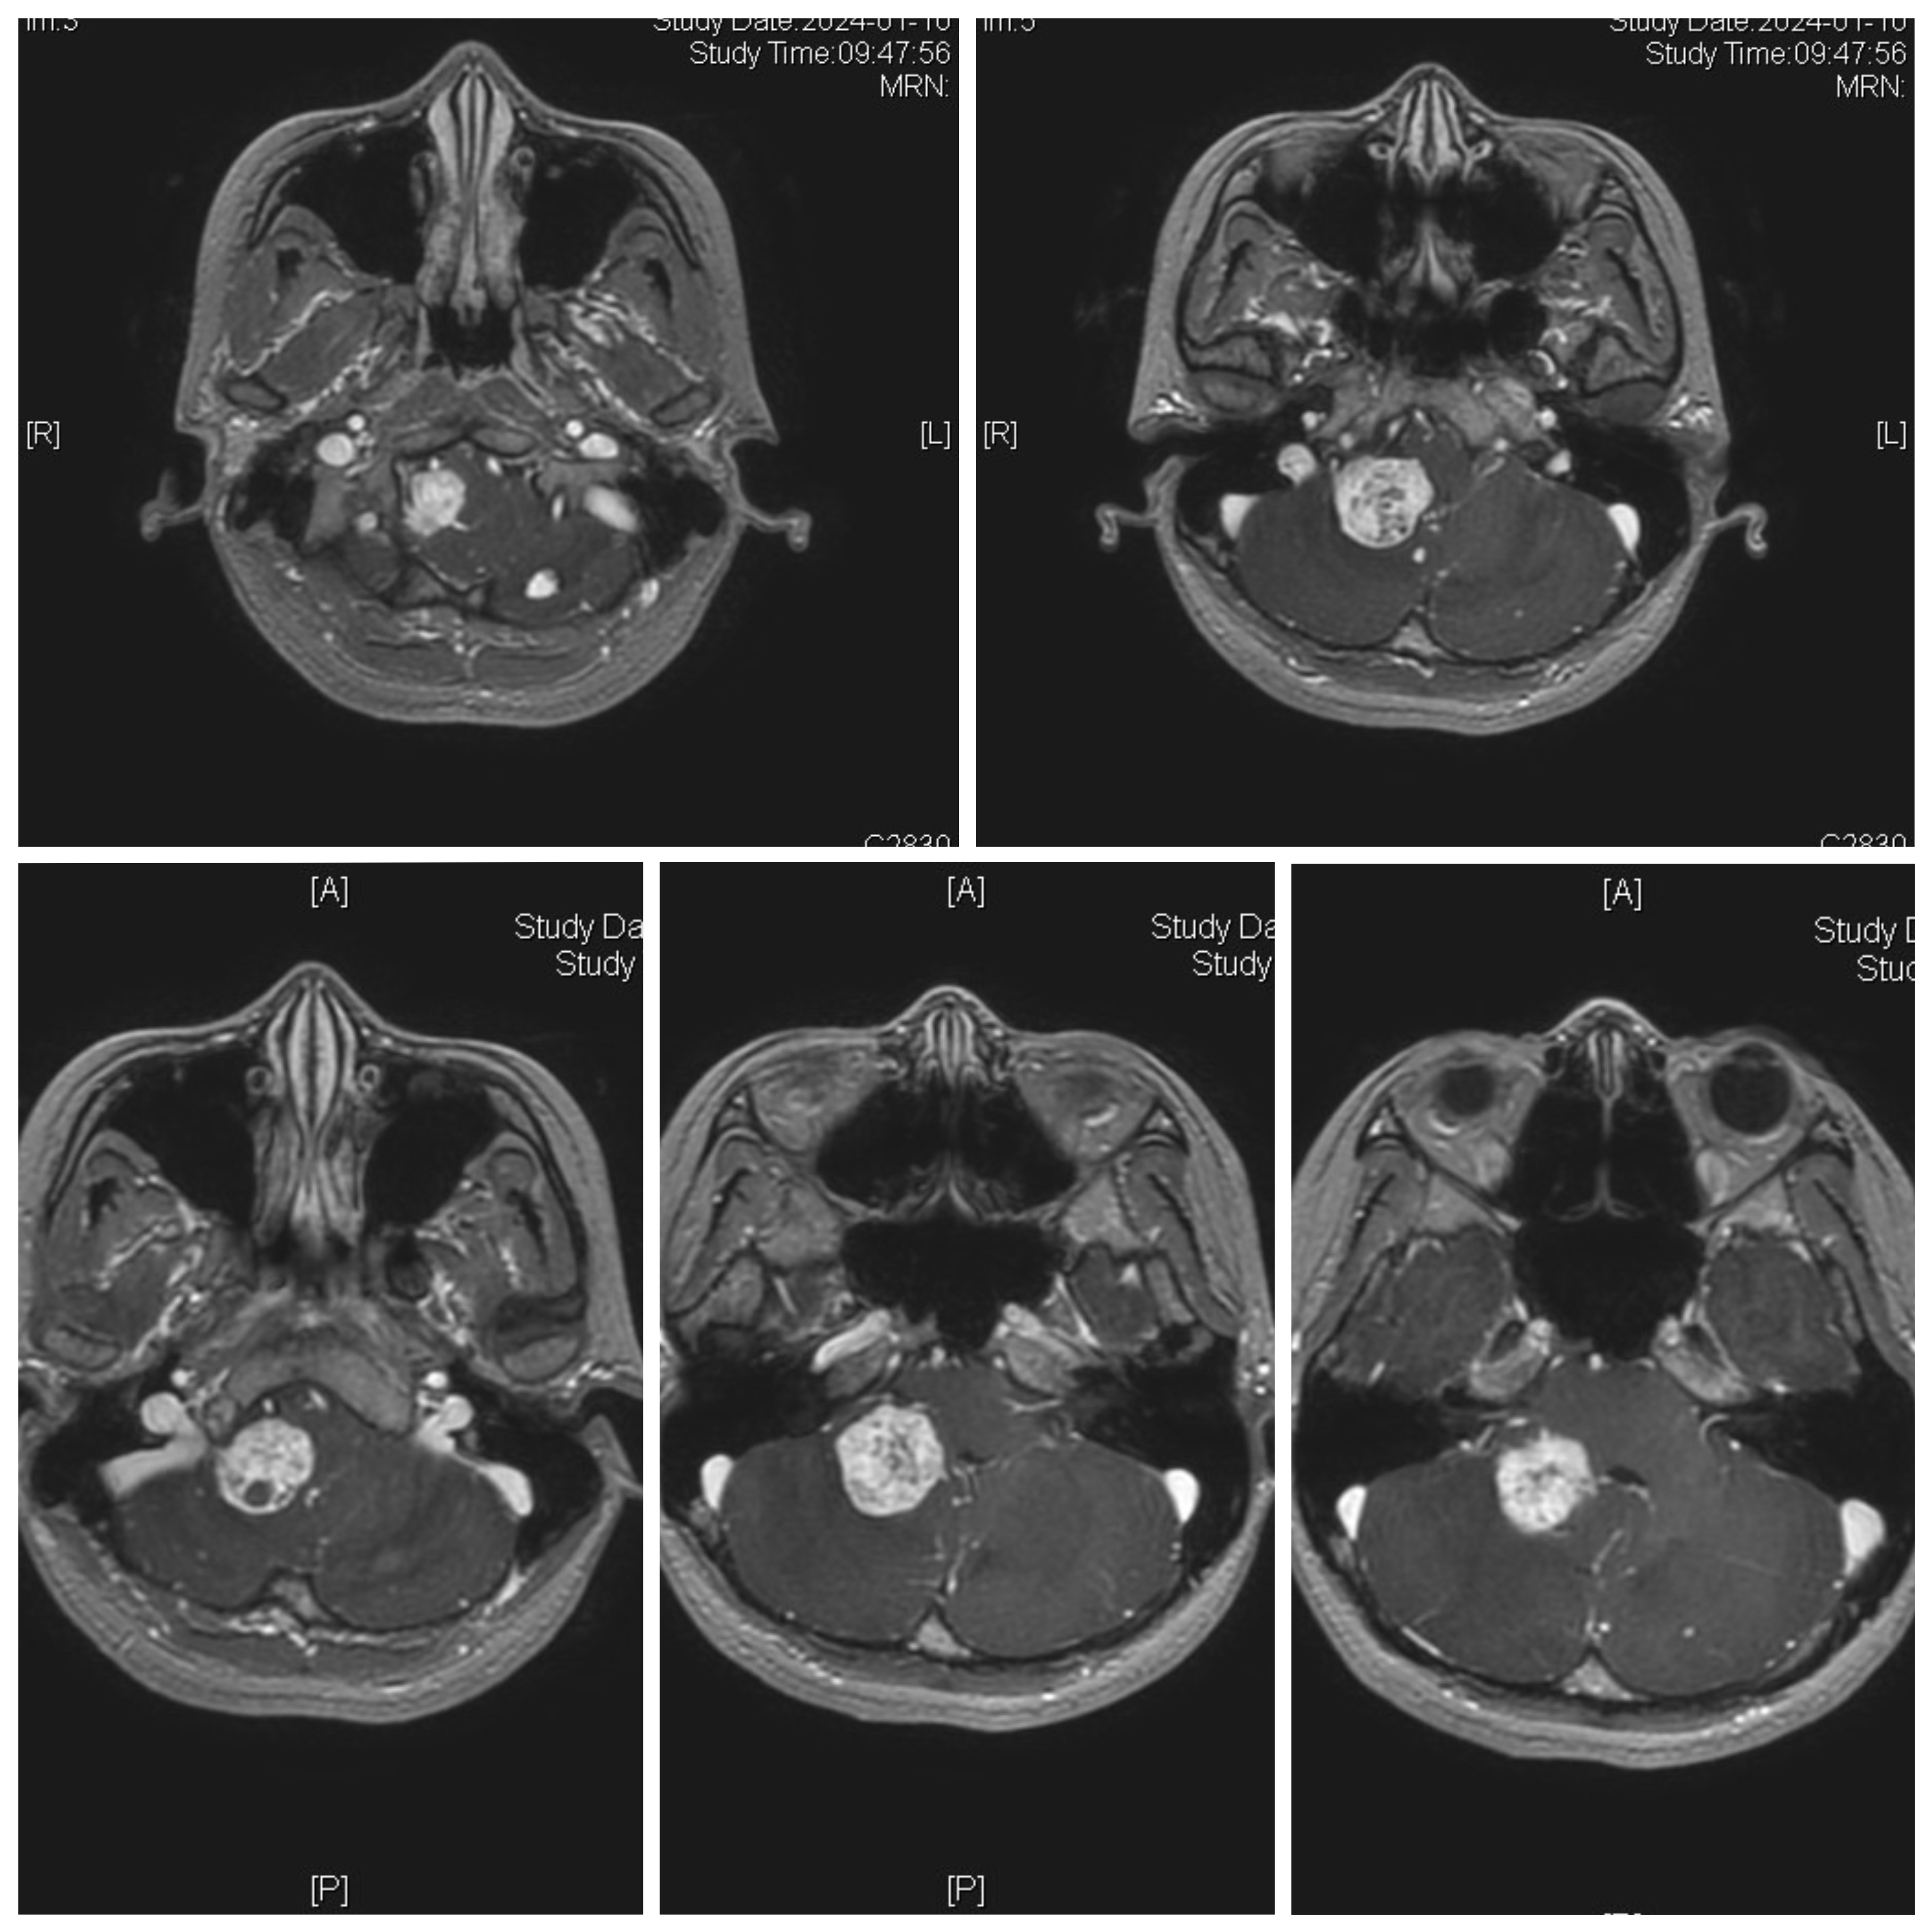

女性患者,26岁,因“间断性头晕1月余。”于2024-01-08入院。

患者1月余前感冒后出现头晕,伴头痛,伴恶心、呕吐。

家族史:患者母亲诊断多发小脑血管母细胞瘤,在我院手术治疗。

体检发现肝脏多发囊肿、右肾囊肿、胰腺多发囊肿。

诊断:延髓血管母细胞瘤

von Hippel-Lindau综合征